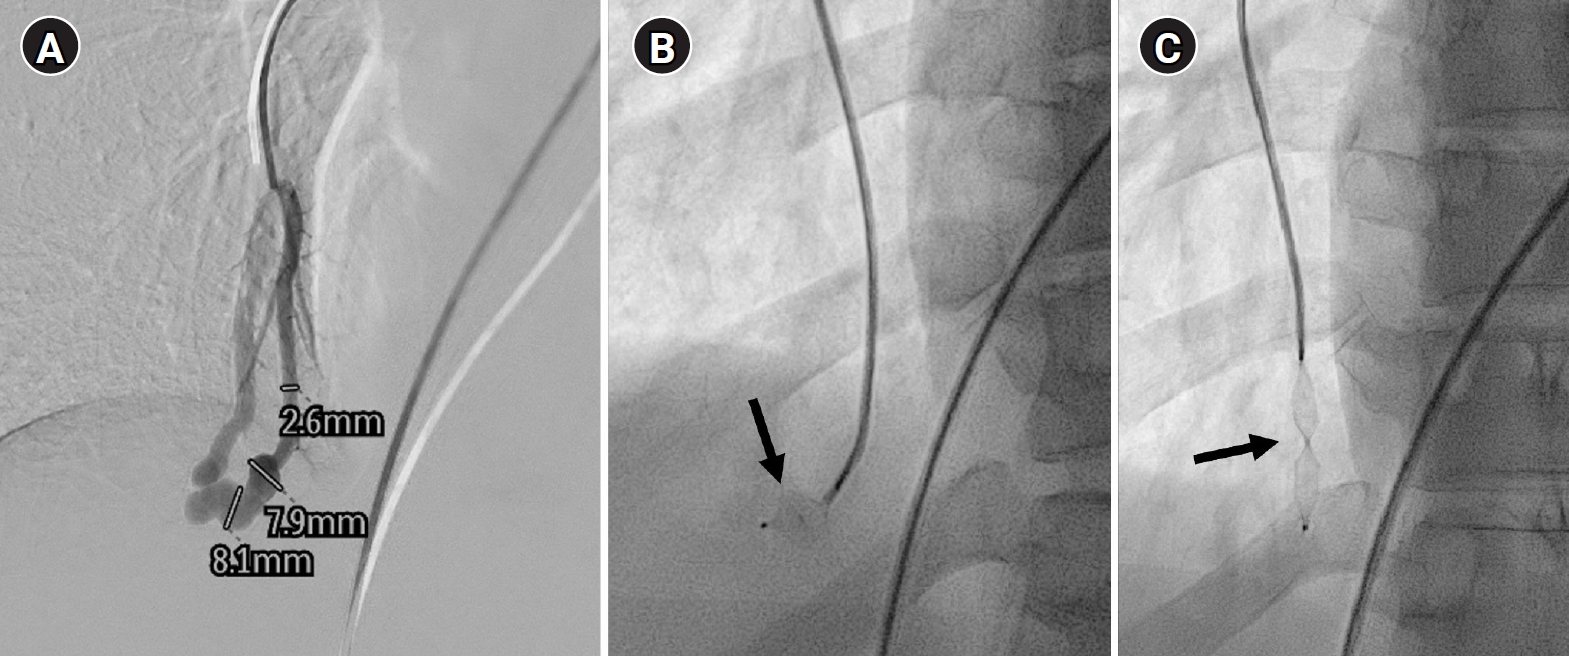

Fig. 5.

Embolization procedure in a patient with a feeding artery diameter of 2.6 mm and a venous sac diameter of 8 mm in the right lower lobe. (A) Selective angiography of the right lower lobe pulmonary arteriovenous malformation. (B) A 7 mm Amplatzer vascular plug type IV (arrow) was deployed into an approximately 8 mm venous sac, and it was determined that this would not provide adequate embolization effect. (C) By repositioning the Amplatzer plug and deploying it at the distal part of the feeding artery (arrow), it becomes clear that an Amplatzer vascular plug sufficiently larger than the feeding artery’s size is needed to effectively achieve embolization.

kjir-2026-00010f5.jpg